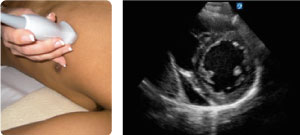

VISTA DEL EJE CORTO PARAESTERNAL

Identifique el VD y el VI al nivel de los músculos papilares. Gire el transductor 90º hacia la derecha desde la vista del eje largo dirigiéndolo hacia el hombro izquierdo del paciente y manteniendo el marcador de orientación en la posición entre las 1 y las 2. Es la mejor vista para observar la movilidad y contractilidad global del VI y el grosor de la pared.